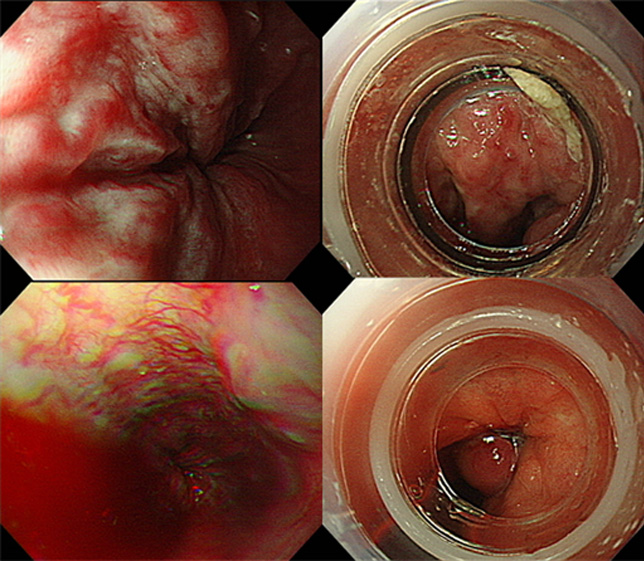

- 합병증은 식도, 위 정맥류 출혈, 간경변성 복수, 간성뇌증, 간신증후군, 간암의 발생이 있습니다.

- 위험요인으로 B,C형 만성간염자, 알코올, 흡연등이 잘알려져 있습니다. 특히 간염 바이러스는 간암의 가장 중요한 원인으로 알려져 있으며, B,C 형 간염이 전체 간암 발생의 75~80%정도 중요합니다. 따라서 B,C형 만성 간염이 있는 위험군 환자들은 조기진단을 위한 정기적인 진찰 및 검사가 필요합니다.

- 진단을 위해 필요한 검사는 간초음파, 간복부전산화단층촬영, 간 조영증강 MRI, 혈관조영술, 간조직검사, 암 표지자로서 알파태아단백(aFP)이 있습니다.

- 치료는 병기에 따라, 환자 상태에 따라 다양한 방법이 있습니다. 수술적 방법으로 간절제술, 간이식이 있으며, 국소치료술로 고주파열치료술, 에탄올주입술이 있으며, 그 외 경동맥화학색전술, 체외 방사선치료, 전신 항암요법이 있습니다. 이는 환자 상태 및 병기에 따라 선택되어 시행할 수 있습니다.